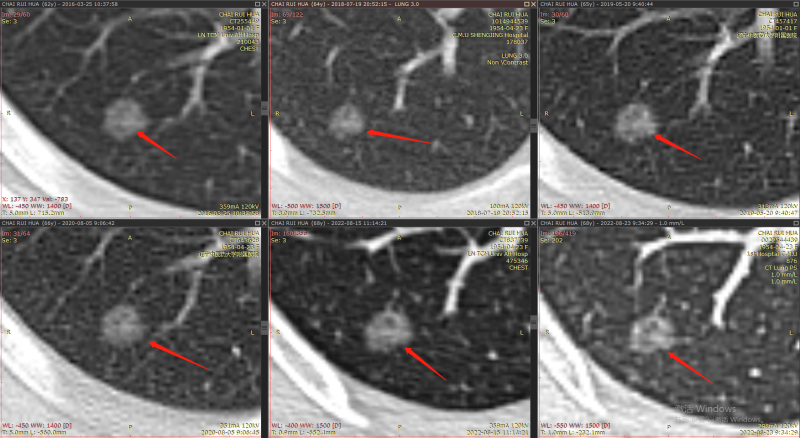

结节1:

2013年

2016年-2022年

右肺下叶背段纯磨玻璃结节,最大截面约0.9cm×0.9cm,平均CT值约-431Hu,结节呈类圆形,其中可见小空泡,病灶边界清楚,与9年前CT片比较,病灶密度、大小均无明显变化,考虑为微浸润性腺癌-浸润性腺癌,以微浸润性腺癌可能性大。